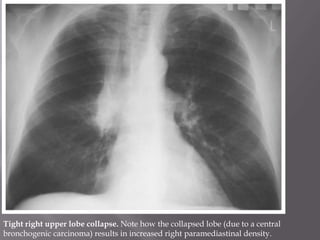

Tight right upper lobe collapse. Note how the collapsed lobe (due to a central

bronchogenic carcinoma) results in increased right paramediastinal density.